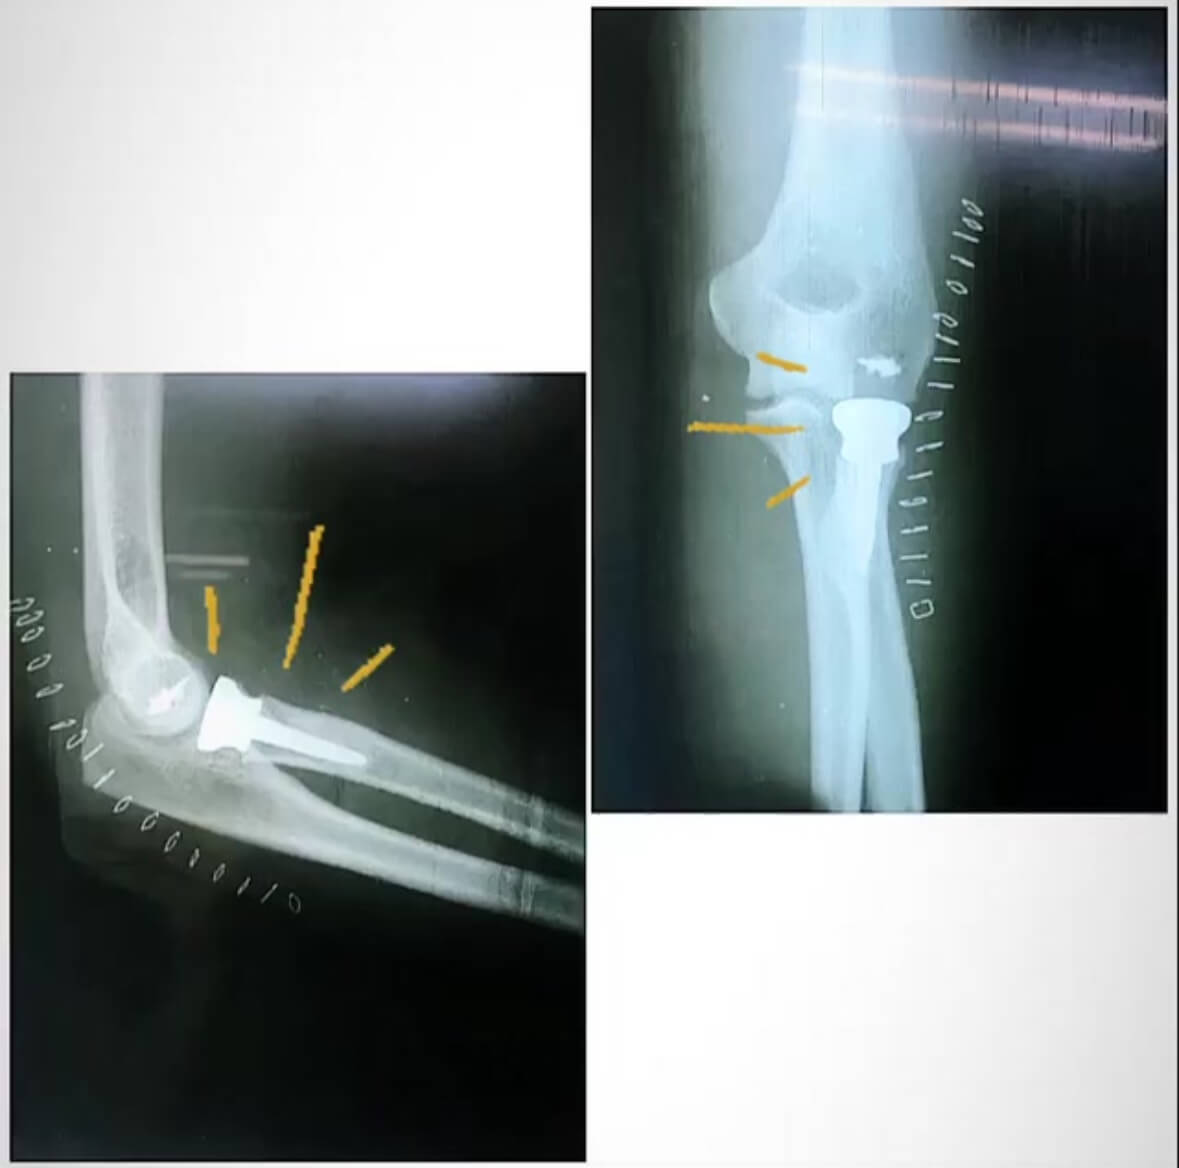

ANTES: Luxofractura codo derecho: - en emergencia se reduce, se hacen diagnósticos y planificamos cirugía.

DESPUÉS: Luxofractura de codo post cirugía y en rehabilitación, con adecuados movimientos en flexoextensión y pronosupinación.